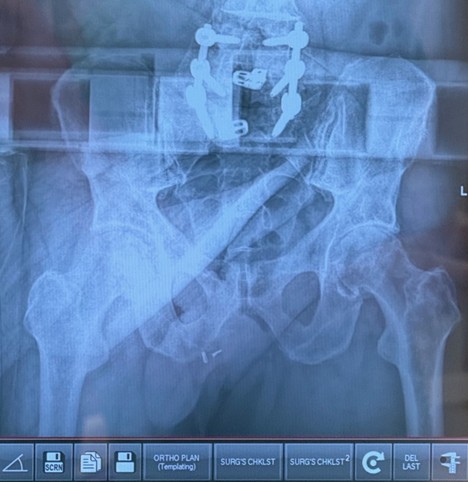

Figure 5. Intra-op AP Pelvis radiograph with Radlink demonstrating advanced left hip osteoarthritis.

Intra-operative Radiograph

Figure 7.